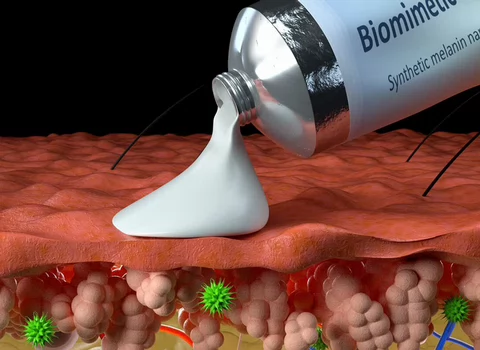

La ingeniería regenerativa es un campo nuevo y emocionante que se define como la convergencia de los avances en la ciencia e ingeniería de materiales, células madre y biología del desarrollo, ciencias físicas y la aplicación clínica para desarrollar herramientas escalables y confiables que permitan la regeneración ó reconstrucción de tejidos complejos y órganos. Puede considerarse un campo que busca facilitar la implementación de la medicina regenerativa para todos.

Con este objetivo, profesores de la Escuela de Ingeniería McCormick y de la Escuela de Medicina Feinberg convergen para participar en investigaciones y educación a través del Instituto Querrey Simpson de Ingeniería Regenerativa de la Universidad Northwestern (QSI RENU), que liderará la iniciativa para desarrollar y traducir tecnologías transformadoras que capaciten a nuestro cuerpo para sanar.